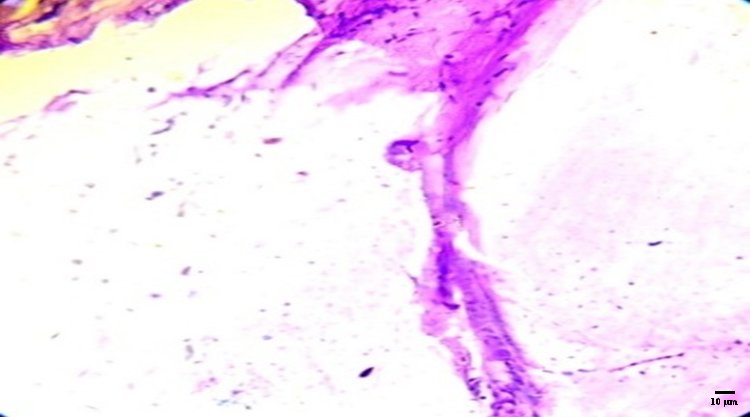

The histological section of hoof tissue infected with candida albicans are shown in fig. 8. The tissue displays abundant fungal structures, including pseudohyphae, blastospores (yeast cells), and hyphal elements, indicating active fungal invasion and tissue disruption [26]. In contrast, Fig. 9 (hoof tissue treated with the optimized nail serum) reveals a marked reduction in fungal structures, with no visible pseudohyphae, blastospores, or hyphae. The hoof tissue architecture appears preserved, indicating that treatment with the serum significantly decreased fungal growth. Similarly, fig. 10 (hoof tissue treated with the marketed formulation) also shows the absence of fungal elements, maintaining the integrity of the tissue. The substantial reduction in fungal colonization observed in fig. 9 demonstrates that the developed nail serum effectively inhibits candida albicans growth. The histopathological results indicate that the serum formulation exhibits antifungal efficacy comparable to the marketed product, thereby supporting its potential use in treating fungal infections of the nail or hoof tissue.

Fig. 9: Histopathology section of porcine hoof nail tissue treated with the optimized nail serum

Fig. 10: Histopathology section of hoof nail tissue treated with the marketed formulation